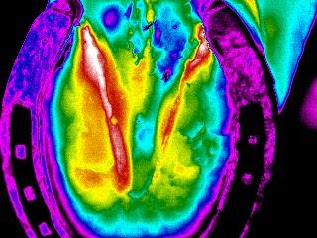

Este aumento de temperatura en el miembro posterior izquierdo, resultó ser un desgarre

muscular.

Absceso en zona plantar del casco